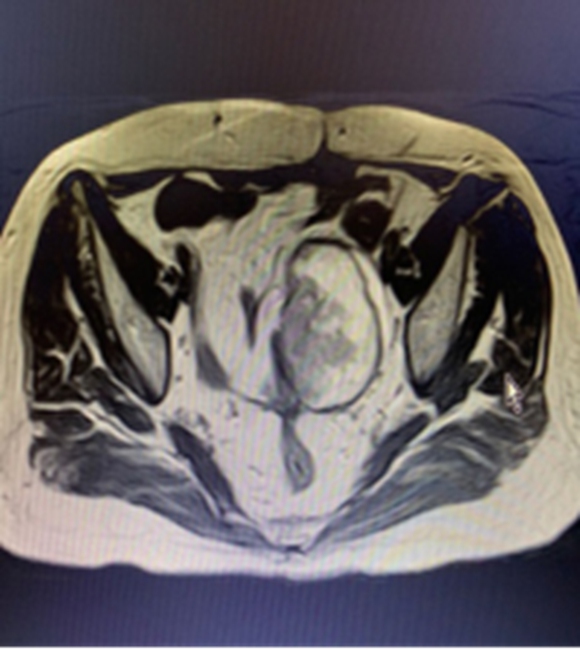

(经详细检查确定,童女士腹腔粘连较重,肿瘤位于盆底,直径10cm大小,与周围肠管,膀胱,输尿管,血管,神经紧密相连,广泛粘连。)

手术历时12个小时,妇瘤病院胡艳副主任医师携同普外科张吉成主任医师,成功完成了高度复杂的膜间隙手术,及部分乙状结肠切除和盆腔肿块切除,最大限度的保留了正常脏器组织功能,患者术后没有出现吻合口瘘、阴道膀胱瘘、阴道直肠瘘等并发症。目前董女士正在术后恢复中,状态良好。

(手术切除透明细胞癌实体瘤大小约8*8.5*9cm,被覆部分乙状结肠肠管,结肠带,脂肪组织,残端宫颈,盆底周围软组织、血管等。)